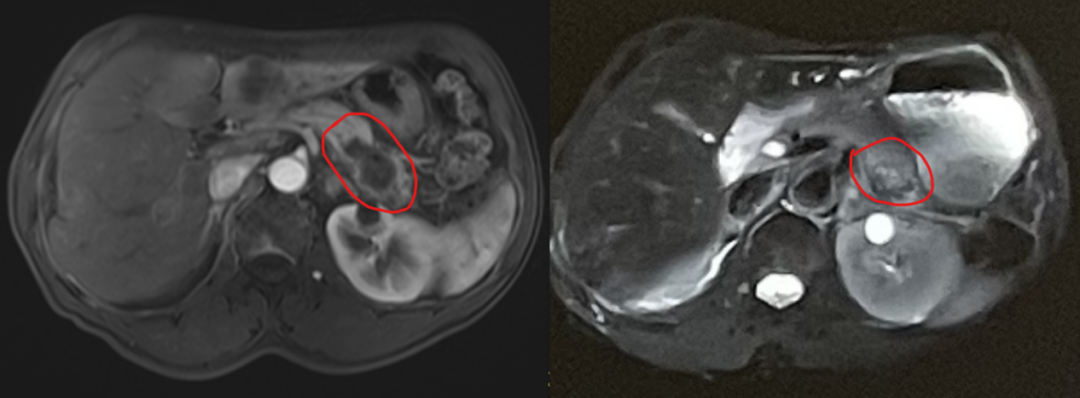

以下为部分病灶碳离子放疗后的变化,左边为放疗前,右边为放疗后1月。

走投无路之下,家人在病友群中了解到重离子治疗对胰腺癌非常有效。经过多方咨询和讨论,一家人将目光锁定在了目前国内胰腺癌重离子治疗最有经验的武威重离子中心(国内首台自主研发的重离子治疗装置)。经过我科(放疗六科)陈威佐主任的电话及微信咨询,一家人重燃信心,一路从天府之国到西北首府。到达医院后,我们对朴叔做了详细的系统性检查。检查结果很不理想,除了肝脏多发的转移,还发现了腹壁下的转移结节。此时复查CA199已超过了12800U/ml。 每周常规进行的重离子专家多学科会诊上,朴叔的病例进过专家们专业的讨论。主管重离子治疗的张雁山副院长总结:虽然朴叔已经对胰腺癌一线治疗的所有药物产生了耐药性,治疗难度大,但病理中CPS表达较高,碳离子的治疗可以在增加局部控制率的基础上,重塑免疫微环境,使患者有机会重新在免疫治疗中获益。朴先生一家人也很坚持:“哪怕全身药物治疗无效了,只要帮我父亲控制住目前发现的病灶,现在医学发展这么快,说不定我父亲就能等到新的靶向药物问世”。 就这样,朴先生接受了为期一个月共15次的重离子治疗(肝脏60Gy(RBE)/15Fx,胰腺58.5Gy(RBE)/14Fx),在基本无任何副作用的治疗结束后,肿瘤标志物下降至9450U/ml。后于2025年2月(治疗结束1月)接受了全面复查,当地复查CA199降至1975U/ml,放疗过的病灶较前均明显减小了。在随访电话里,朴叔告诉我们,一项针对KRAS G12D突变的靶向药物的临床试验对他张开了臂膀,他将在抗癌路上继续坚定前行。